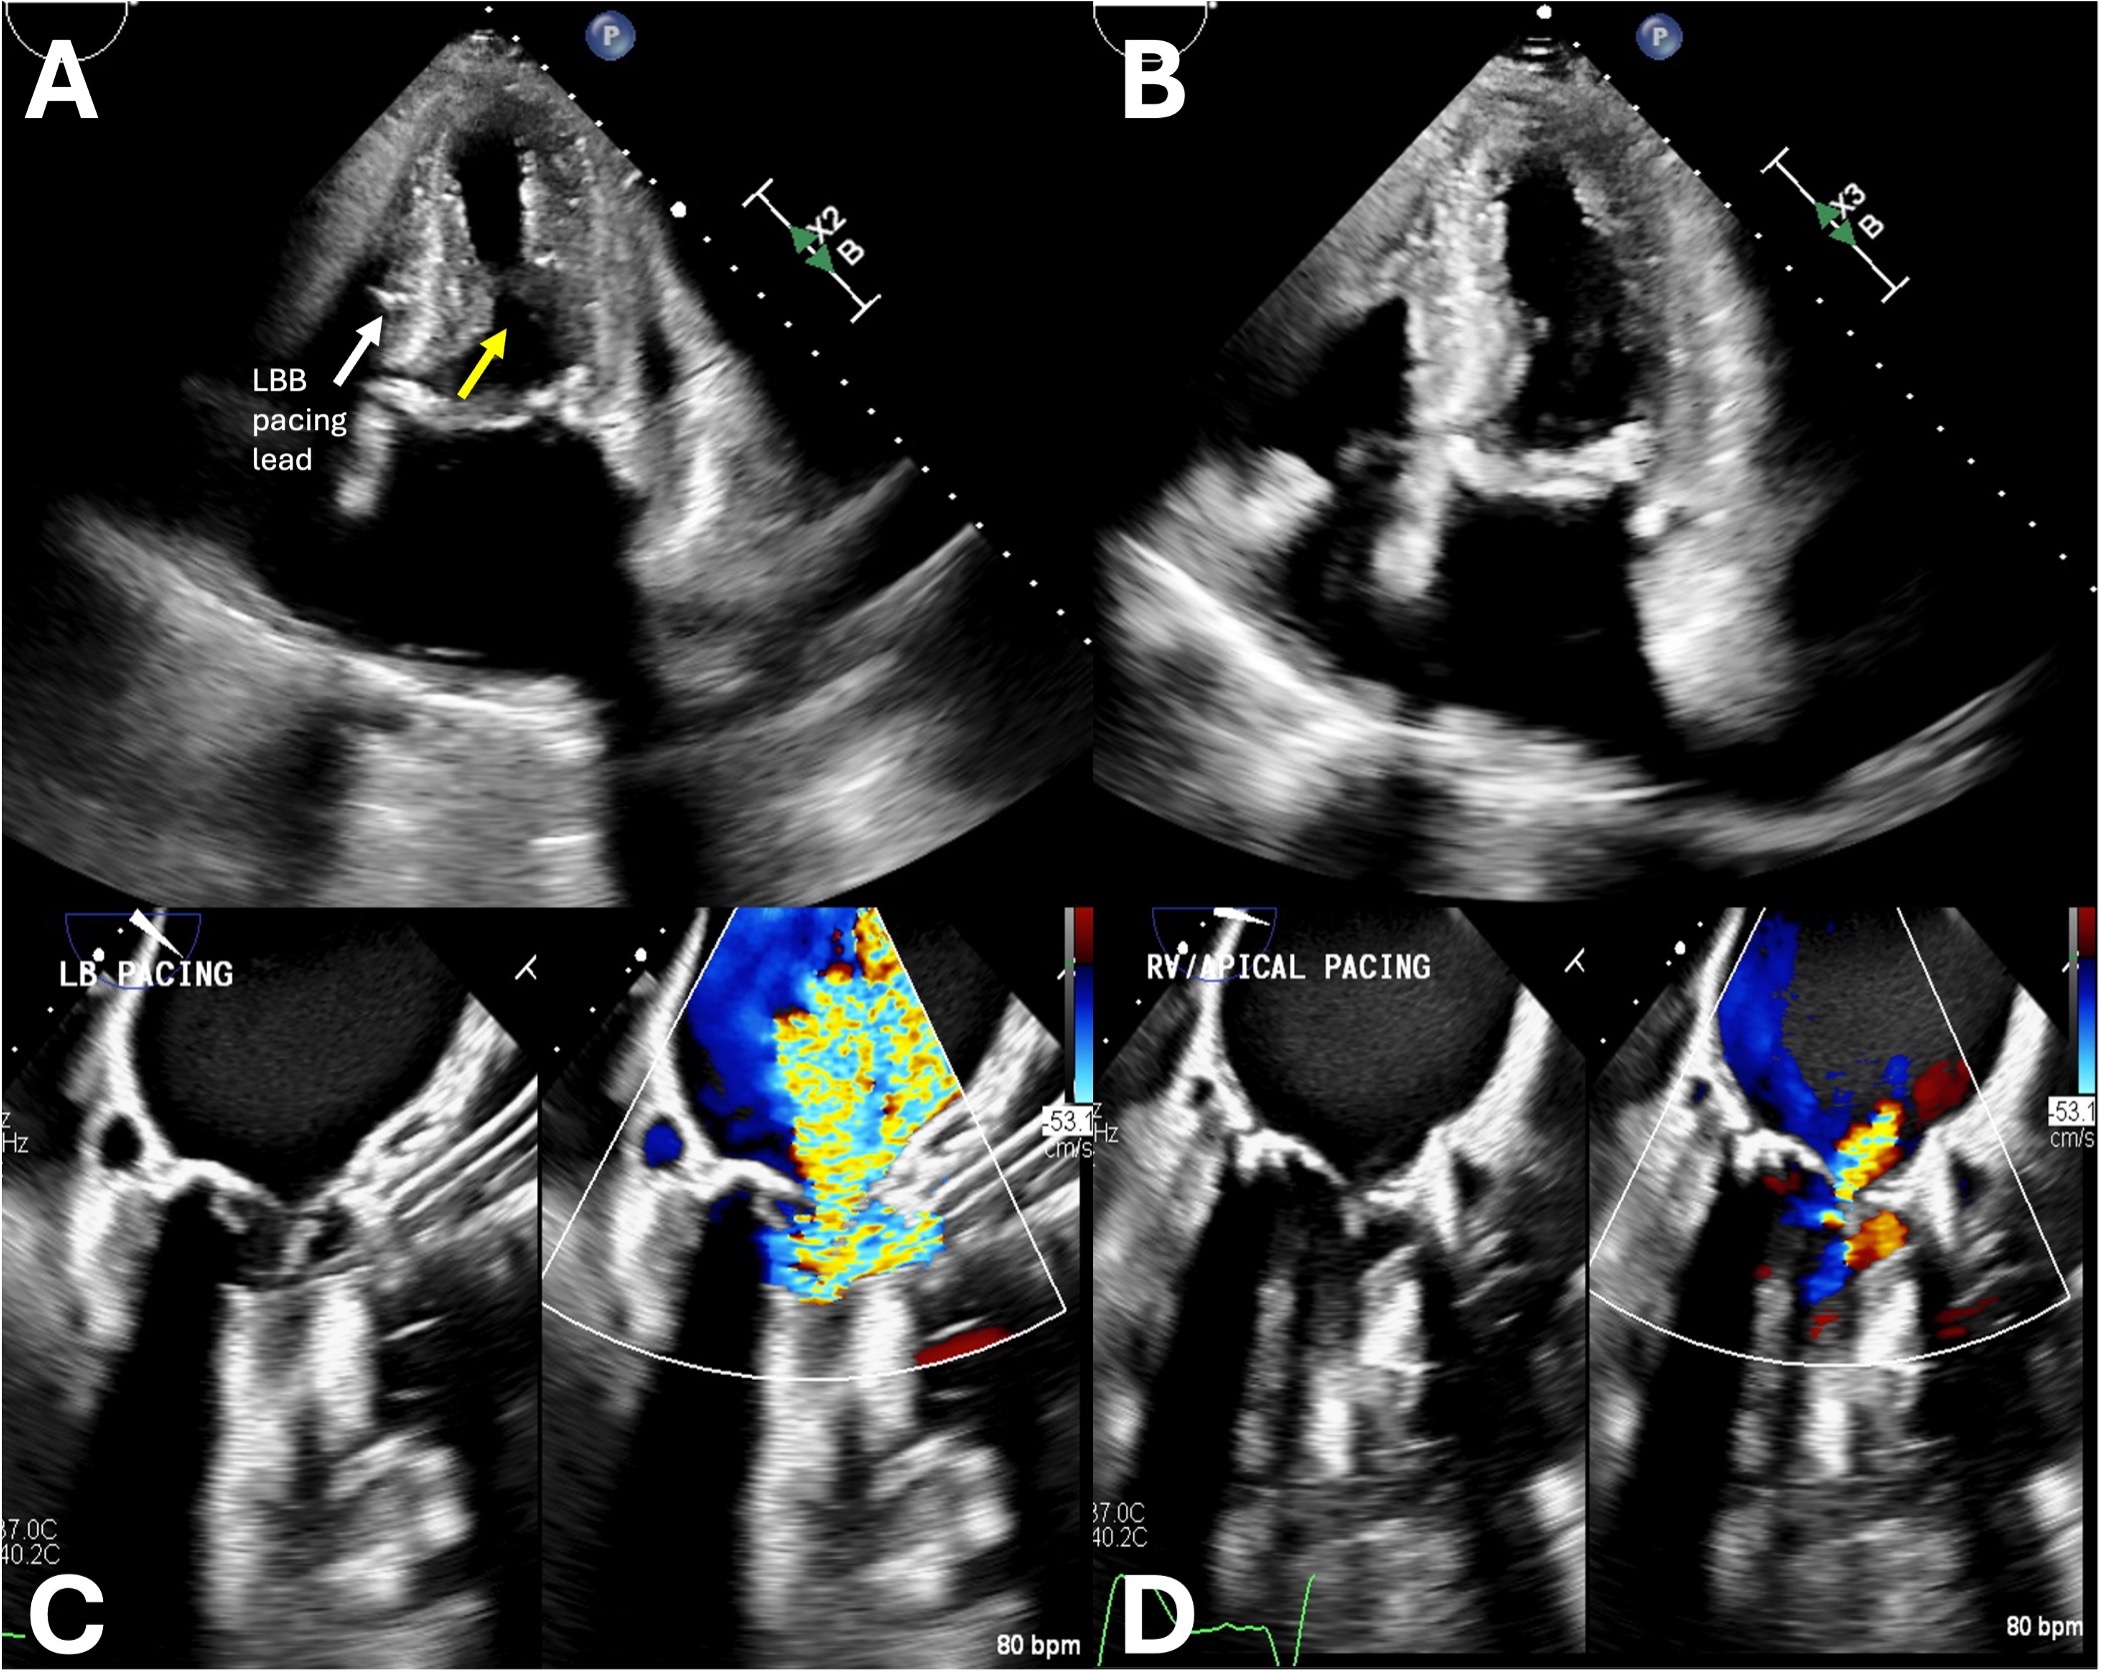

Abstract Body (Do not enter title and authors here): Description of Case: An 81-year old-female with paroxysmal atrial fibrillation (AF) and severe aortic stenosis presented with AF with rapid ventricular response and volume overload. She had undergone an uncomplicated transcatheter aortic valve replacement (TAVR) 14 days prior with post procedure echocardiogram (TTE) demonstrating ejection fraction greater than 70%, a mean gradient across the TAVR valve of 11 mmHg, and mild mitral regurgitation (MR). Management included diuresis, rate control, and a failed cardioversion. TEE at the time of cardioversion, while tachycardic, demonstrated systolic anterior motion of the mitral valve (SAM) but no gradient across the aortic valve. She underwent atrioventricular (AV) junction ablation and placement of a left bundle branch area pacing (LBBAP) lead. Immediately post-procedure, she developed acute dyspnea and a new systolic murmur. Right heart catheterization revealed pulmonary artery pressure 90/30 mmHg and wedge pressure 39 mmHg with a prominent v-wave, and cardiac index of 1.6 L/min/m2. A simultaneous LV-AO pressure tracing demonstrated a gradient of 52 mmHg. TTE revealed a late-peaking doppler signal across the aortic valve with a peak velocity of 4 m/s, SAM, and severe MR. An Impella CP was placed for circulatory support. TTE revealed the LBBAP lead was adjacent to a 1.8 cm basal septal bulge (Figure 1). The next day, a transvenous RV apical pacing lead was placed, and simulatenous LV-AO pressure tracing revealed a peak-to-peak gradient of 45 mmHg during LBBAP, which immediately decreased to 5 mmHg with RV apical pacing (Figure 2). This led to a decrease in MR from severe to mild. Given the dynamic nature of the obstruction, alcohol septal ablation was performed. The Impella CP was removed and vasopressors were weaned. A permanent RV apical lead was added and used for pacing. The patient remained hemodynamically stable and was discharged to rehabilitation.

Discussion: This case highlights a report of dynamic left ventricular outflow tract (LVOT) obstruction precipitated by LBBAP in a patient post-TAVR who previously did not have evidence of LVOT obstruction. Previously, RV apical pacing was a seldom used treatment for obstructive hypertrophic cardiomyopathy. Changing the pacing location to RV apical pacing instantly resolved the LVOT obstruction highlighting the need to be wary of pacing strategies in post TAVR patients who may have septal hypertrophy and may be at risk of LVOT obstruction secondary to LBBAP.